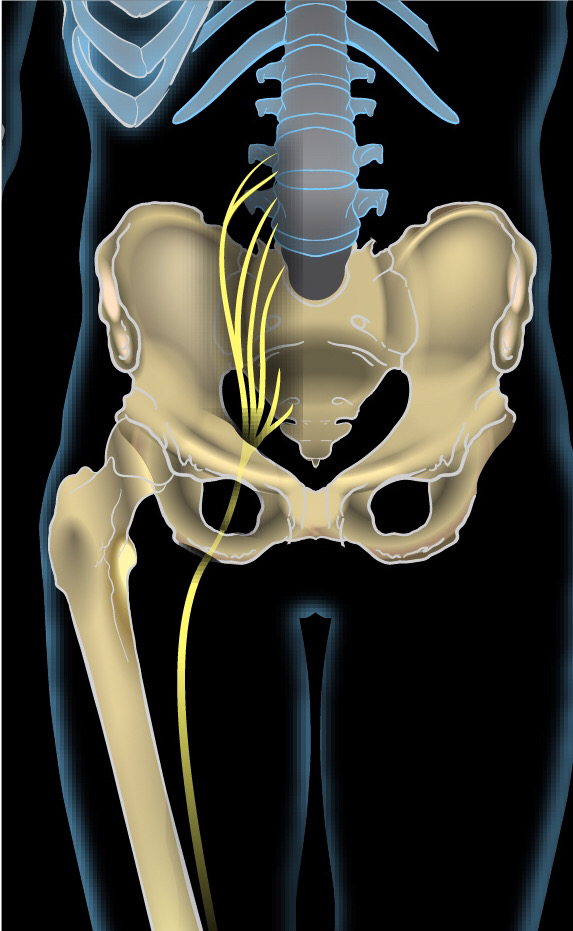

坐骨神経とは腰から足に向かって伸びる体の中でもっとも大きな神経です。この坐骨神経がなんらかの圧迫や刺激が加わることで現れる、痛みや痺れなどの症状を言います。

多くの方は、腰の痛みから始まりお尻や太もも、すね、足先などに違和感から痛み、痺れが現れてきます。

しかし坐骨神経は腰から足の先まで繋がっているため、圧迫や刺激をする場所が腰だけに限らず股関節や膝関節、足首に原因があることも考えられます。

坐骨神経がお尻や太ももの筋肉のコリや血行障害を痛みという信号で脳に送っていて、神経そのものが痛い訳ではありません。